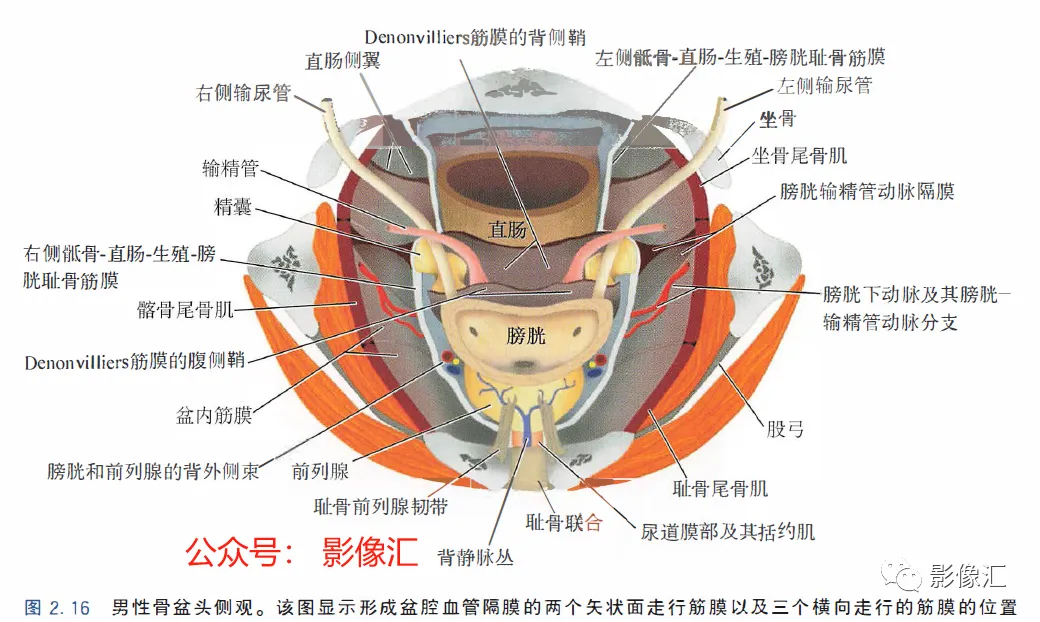

在盆腔侧壁和下壁肌肉骨髂层与前壁层腹膜隐窝之间头侧存在“腹膜下盆腔间隙”,该间隙中线处为盆腔内脏,两侧面为神经血管蒂。该间隙同时含有丰富的纤维脂肪组织,在头侧与腹膜外脂肪组织相延续,侧方通过坐骨切迹与臀部及会阴部的脂肪组织相延续。腹膜下盆腔间隙中不同的细胞-纤维鞘分隔,分隔并不完整,这些细胞-纤维鞘起自盆腔血管的血管鞘,并与血管伴行,从其起源的盆腔侧壁走行至所相应供血的内脏区域。这些细胞-纤维鞘也被称为“血管隔膜”。其由纤维结缔组织、弹性纤维、脂肪组织和平滑肌纤维组成。很重要的是要知道位于盆腔内部的这些筋膜的分布,该筋膜内存在着盆腔脏器所有的供血血管及神经支配,并形成根治性前列腺切除术中采用的不同手术分离平面。

根据示意图可显示五个筋膜(图2.16和图2.17)。上图,前列腺中线正中矢状切面,显示中央带(CZ)、外周带(PZ)和前列腺肌性间质(AFMS)。注意在CZ底部的精囊喙水平缺少前列腺包膜。Denonvilliers筋膜由多个平行走行的鞘组成,头尾走行。在组织学上,其具有平滑肌纤维,血管和神经的纤维弹性结缔组织。在其侧缘,与Farabeuf骶骨-直肠-生殖-膀胱耻骨筋膜的外侧鞘及膀胱输精管动脉的横向隔膜融合。直肠-前列腺手术分离沿形成Denonvilliers筋膜的鞘复合体背侧进行操作。Denonvilliers筋膜是一层疏松的结缔组织。

AFMS:前列腺肌性间质;CZ:中央带;PZ:外周带;SV:精囊;IUS尿道内括约肌。两个矢状面走行筋膜:Farabeuf骶骨-直肠-生殖-膀胱-耻骨鞘(左右各一);三个横轴面走行筋膜:脐-膀胱前筋膜;“生殖动脉隔”;直肠中动脉的隔(Septum of the mid-hae-morrhoiclal artery)。在前列腺,这些鞘也被称为“Retzius前列腺周围筋膜”“前列腺周围筋膜”“前列腺侧带”,或者最近称为“盆内筋膜腹侧面” 。这些筋膜覆盖腺体的侧面和腹侧,在腹侧与前纤维肌性间质(AFMS)融合。供血血管和支配神经在这些鞘内走行。一旦解剖前列腺后部或直肠前平面,这些鞘在前列腺的两侧形成手术分离平面。前列腺“本身”不具有包膜结构;所谓的包膜只是腺样间质聚集所致,而且个体间变异度很大,同时在某些点上并不存在,从而构成McNeal所述的解剖薄弱区域。因此,从实际的角度来看,我们认为虽然前列腺没有自己的包膜结构,但其确实有三个“假包膜":